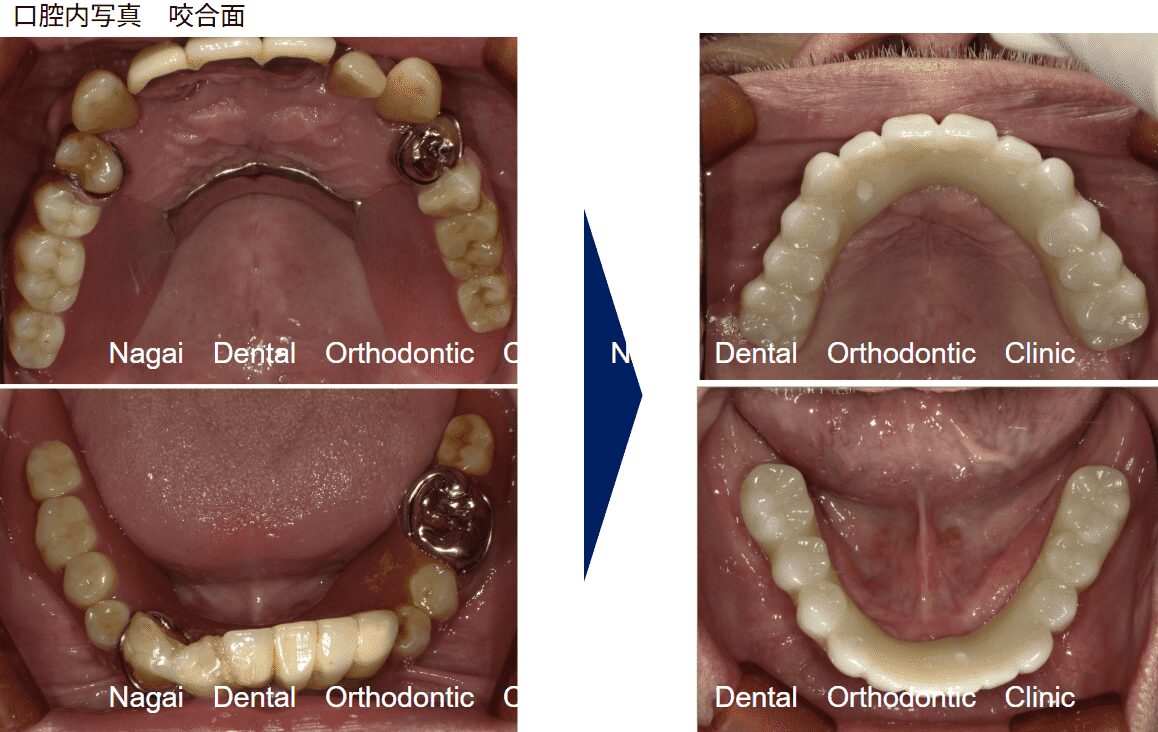

【口腔内の詳細変化】

▲入れ歯による異物感や違和感の軽減を図りました

▲噛み合わせのバランスを整え、咀嚼機能の改善を目指しました

| 年齢/性別 | 40代/男性 |

| 背景 | 上下の入れ歯を使用されていましたが、入れ歯による異物感が強く、咀嚼への支障(硬い食事を避ける等)を理由にご来院されました。初診時、上顎は歯がすべてない状態、下顎は6本の歯が残存している状態でした。 |

| 治療期間 | 約7か月 |

| 費用 | 上顎:3,000,000円 |